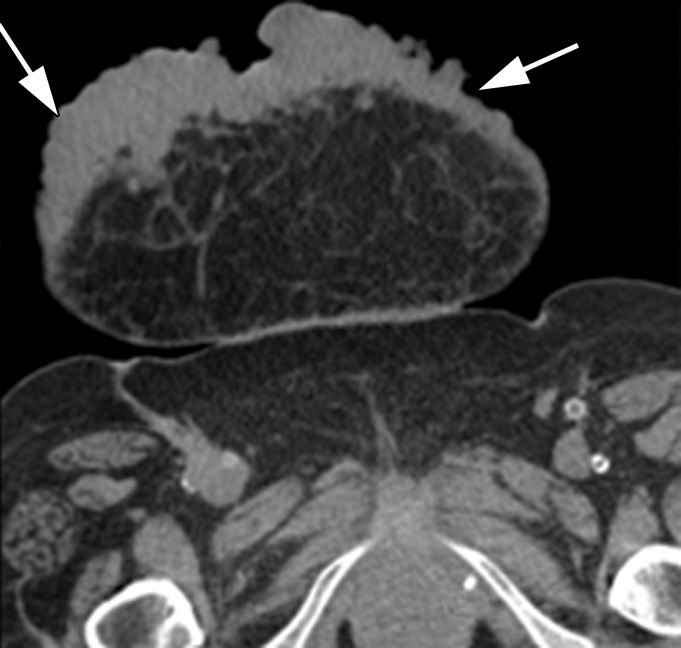

Figure 17a.

Variable appearances of abdominal wall sarcomas in six different patients. Compare the appearances of discrete palpable abdominal wall masses (a–c) to those of superficial ulcerative masses (d–f). (a) Axial CT image in a 38-year-old man shows a well-circumscribed small epithelioid sarcoma (arrow) in the subcutaneous fat (thought to be an inguinal hernia on examination). (b) Axial CT image in a 33-year-old man shows a leiomyosarcoma (arrows) deep in the underlying muscle of the abdomen (the patient also had a tumor in the right thigh [not shown]). (c) Axial CT image in a 21-year-old man shows a large rhabdomyosarcoma (arrow). The patient also had a tumor in the left thigh (not shown). (d) Axial CT image in a 24-year-old man shows a superficial dermatofibrosarcoma protuberans (arrow) that is not grossly ulcerative at imaging, but physical examination showed edematous skin and bleeding. (e) Axial CT image in a 71-year-old woman shows a superficial epithelioid angiosarcoma (arrows) that manifested as a neglected ulcerative wound at presentation. (f) Axial CT image in a 62-year-old woman shows a deep and infiltrating synovial sarcoma (arrows) that manifested as a neglected ulcerative wound at presentation. All diagnoses were confirmed by means of surgical resection or biopsy.